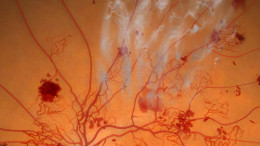

Diabetic retinopathy is a condition in which the retinas small blood vessels become damaged due to uncontrolled diabetes, causing vision problems. Over time, fluid leakage and new abnormal blood vessels can contribute to severe vision loss. Keeping blood sugar levels stable can help prevent or slow down the advancement of the condition.

Acupuncture works to enhance the body's overall function by stimulating specific points known as acupoints. This process encourages the bodys natural ability to heal itself. The primary technique for stimulating these points involves inserting fine, sterile needles into the skin. In addition, the effects can be amplified through heat, pressure, or electrical stimulation. Other methods of stimulating acupoints include massage, cupping, moxibustion, and applying herbal treatments or linaments.